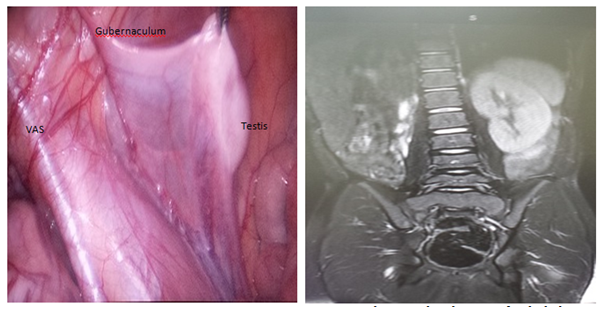

12Year male child was referred from paediatric endocrinology with a diagnosis of right undescended testes. Clinically the testis could not be felt in the inguinal canal. He is a juvenile diabetic and is under treatment for the same and underwent an MRI scan of abdomen which was reported as absence of right kidney and the testes couldn’t be localized. This boy was subjected for diagnostic laparoscopy and the findings were as follows. The right internal ring was closed and a vas deferens was coursed medial to lateral, from the expected origin, terminating at above the internal ring. A gubernaculum was identified emanating from the internal ring coursed proximally towards the right iliac fossa. Our aim was to retrieve tissue for biopsy, to our surprise testes was found at right iliac fossa, far more proximal and separate from the blind ending vas, suspended on a broad vascular pedicle, 1.5cm x 1.0cm in size. Keeping the above findings In view laparoscopic orchiectomy was done and the child had a smooth post operative course. Biopsy has revealed testicular tissue with interstitial fibrosis. The tubules exhibit only sertolicells, occasional leydigcells. There is no evidence of malignancy seen. Closed internal ring with vas deferens coursing medial to lateral, terminating just superior to ring the gubernaculum coursing proximally up the retroperitoneum,terminating at testis.

Figure 1 Closed internal ring with vas deferens coursing medial to lateral,terminating just superior to ring.the gubernaculum coursing proximally up the retroperitoneum,terminating at testis.

Figure 2 Mri showing the absence right kidney.